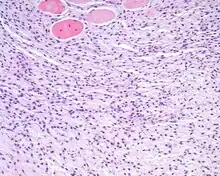

An intermediate power hematoxylin and eosin stained section of an ectomesenchymal chondromyxoid tumor, showing skeletal muscle entrapment. Note the "net-like" appearance (lower portion).[5][6]

An intermediate power hematoxylin and eosin stained section of an ectomesenchymal chondromyxoid tumor, showing skeletal muscle entrapment. Note the "net-like" appearance (lower portion).[5][6] The overlying surface epithelium is intact and unconnected to the well circumscribed, but unencapsulated ectomesenchymal chondromyxoid tumor of the tongue. There are numerous skeletal muscle bundles at the periphery of the tumor.

The overlying surface epithelium is intact and unconnected to the well circumscribed, but unencapsulated ectomesenchymal chondromyxoid tumor of the tongue. There are numerous skeletal muscle bundles at the periphery of the tumor. - The tumor is made up of small round, oval, spindle, or stellate cells that have a very monotonous appearance. There are small dark nuclei with variably amounts of light to basophilic cytoplasm.[1][5][7]